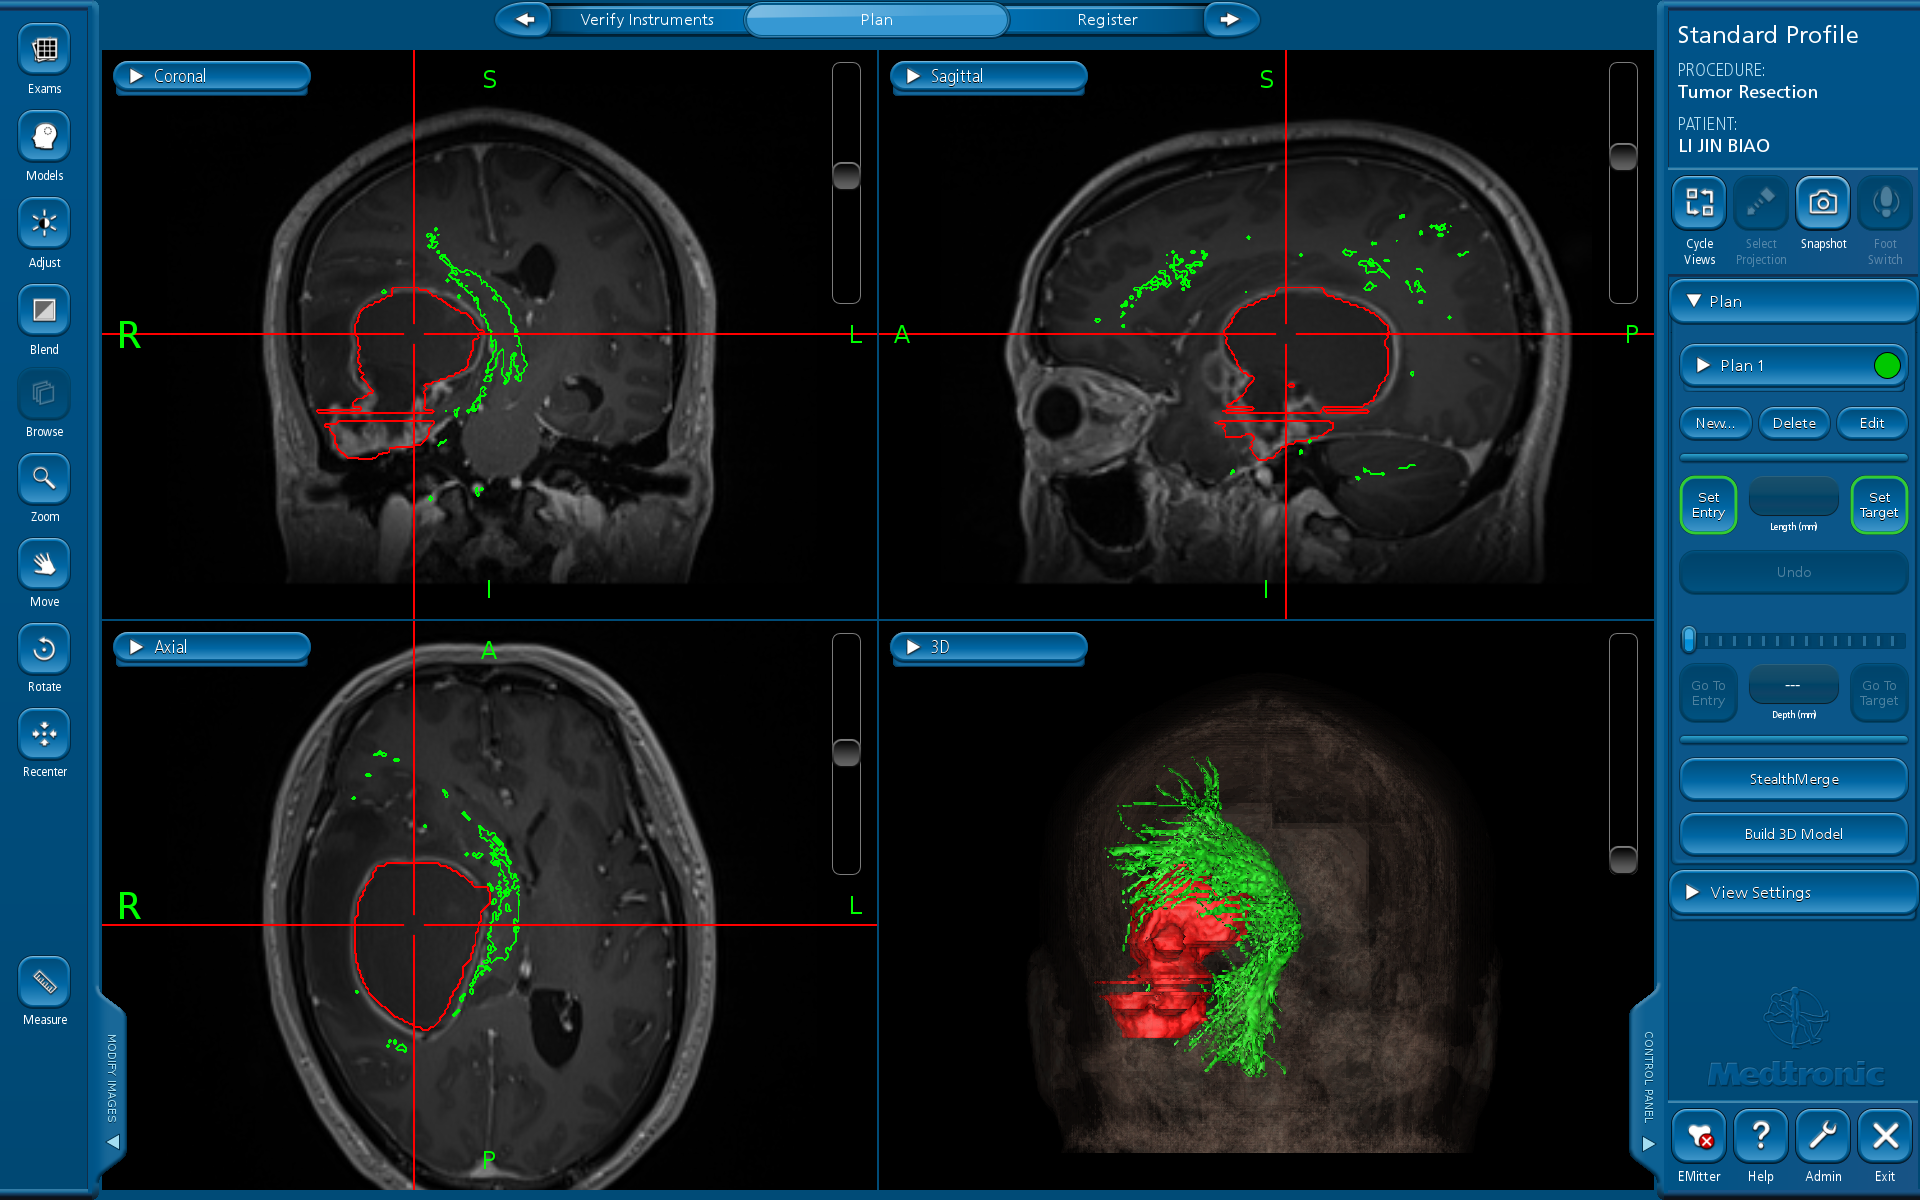

术前导航提示肿瘤与锥体束毗邻